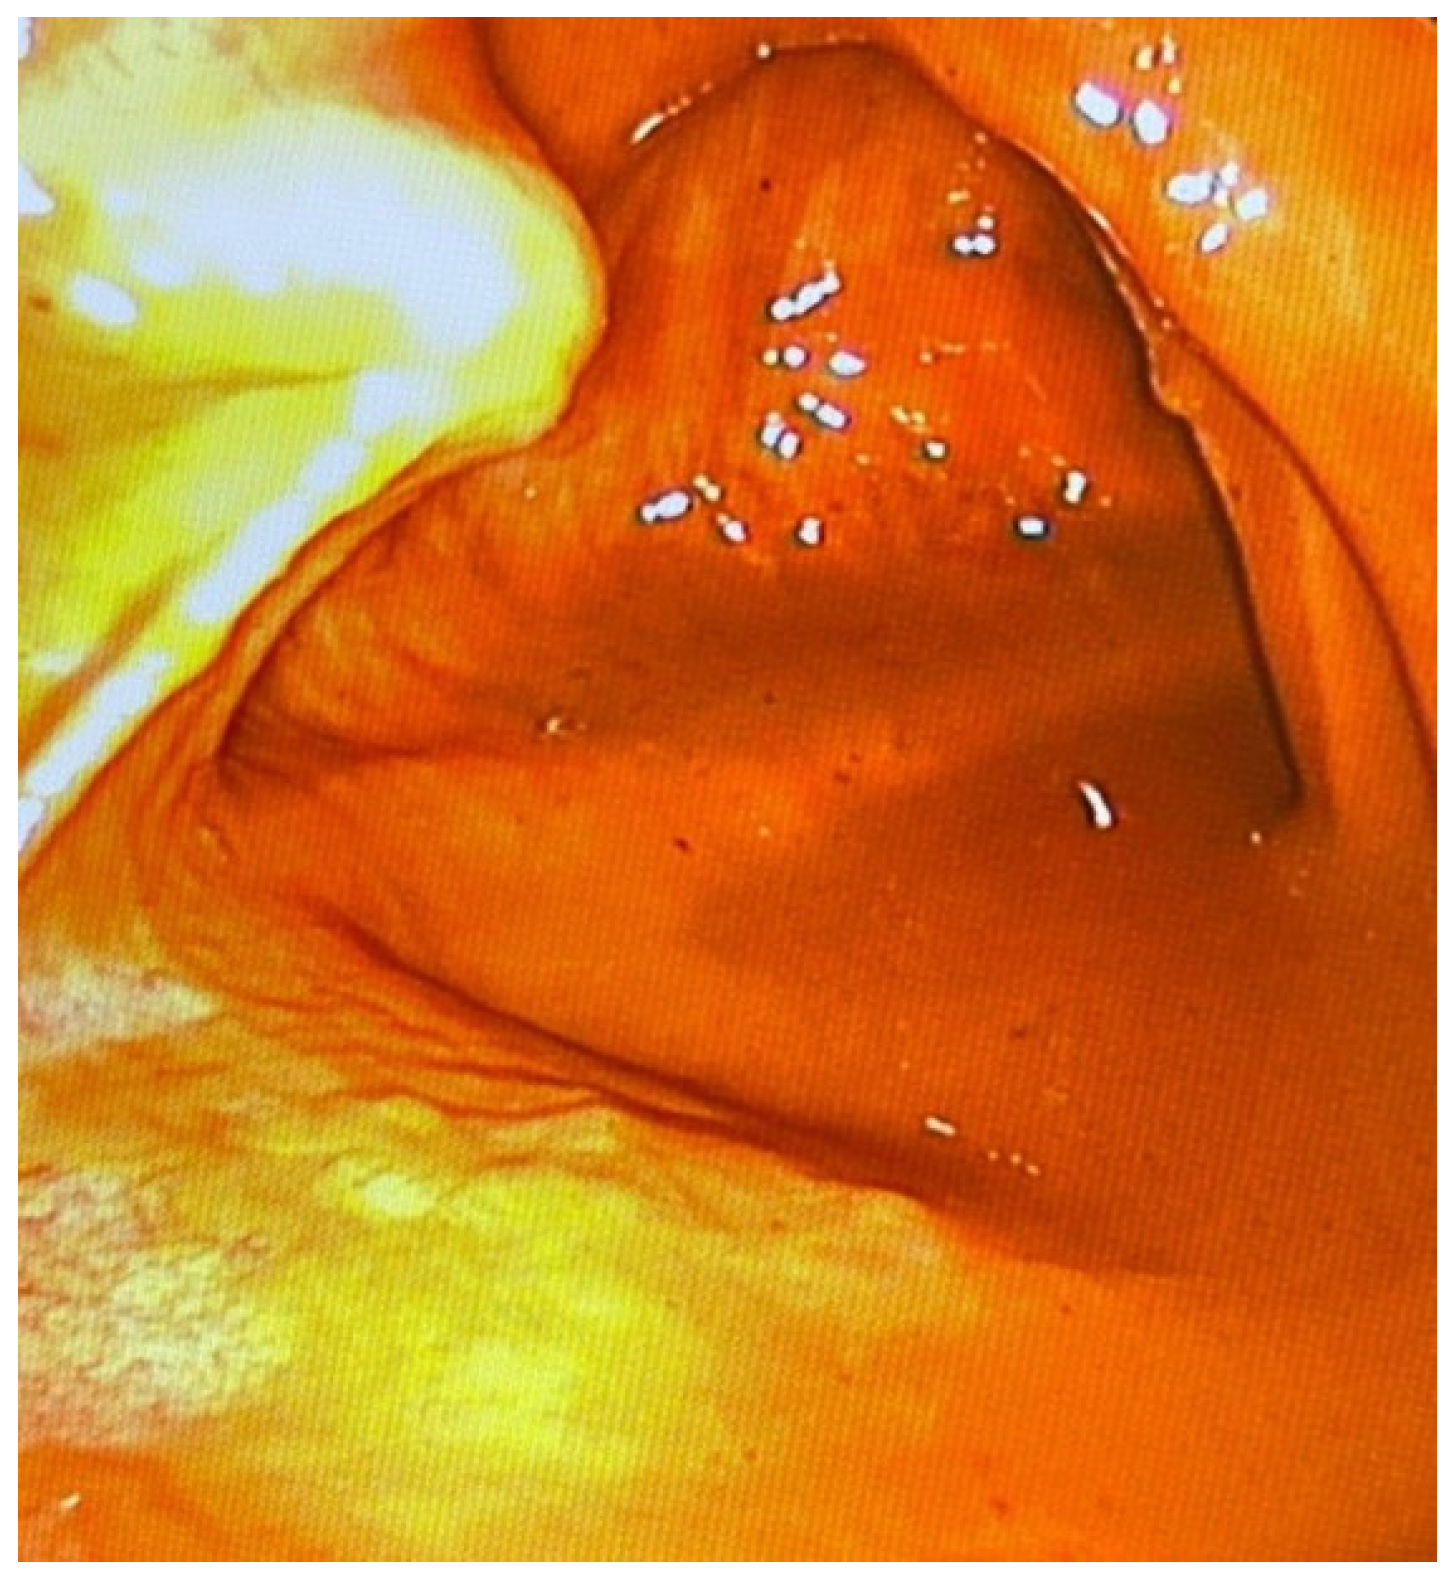

3.2. Establishing a Procedure for Minimally Invasive Post-Mortem Diagnostics Using Endoscopic Techniques

3.3. Clinical Efficiency